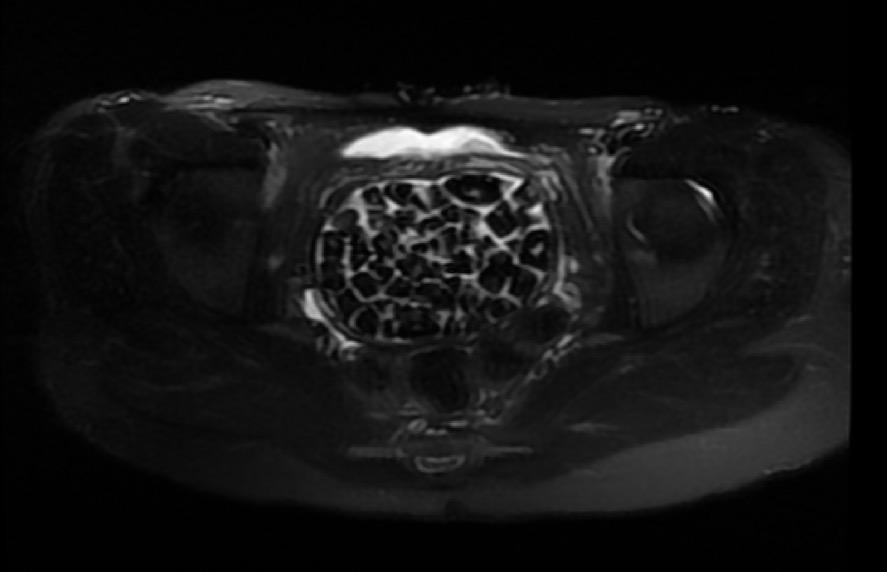

Doğumsal ürolojik hastalıkla dünyaya gelen 21 yaşındaki Fatma Nur Öztürk, şiddetli karın ağrısı şikayetiyle hastaneye gitti, yapılan operasyonla vücudundan 287 adet taş çıkarıldı. Taşlar hem sağlık ekibini hem hasta ve ailesini şok ederken uzmanlar, "Mesaneden vajene ... haberin devamı için tıklayın

VÜCUDUNDAN 287 TANE TAŞ ÇIKARILDI, DOKTORLAR BİLE ŞOK OLDU: "LİTERATÜRDE ÇOK NADİR GÖRÜLEN BİR OLAY" KARIN AĞRISIYLA DOKTORA GİTTİ, VÜCUDUNDAN 287 TANE TAŞ ÇIKARILDI UZMANLAR: "BİZ DE O KADAR TAŞ BEKLEMİYORDUK, ÇOK ŞAŞIRDIK"